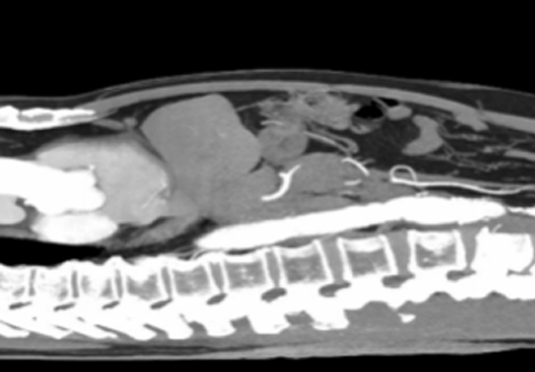

微創射頻消融術

適用于微創射頻熱消融術治療患者,引進權威醫療團體輔助引流。